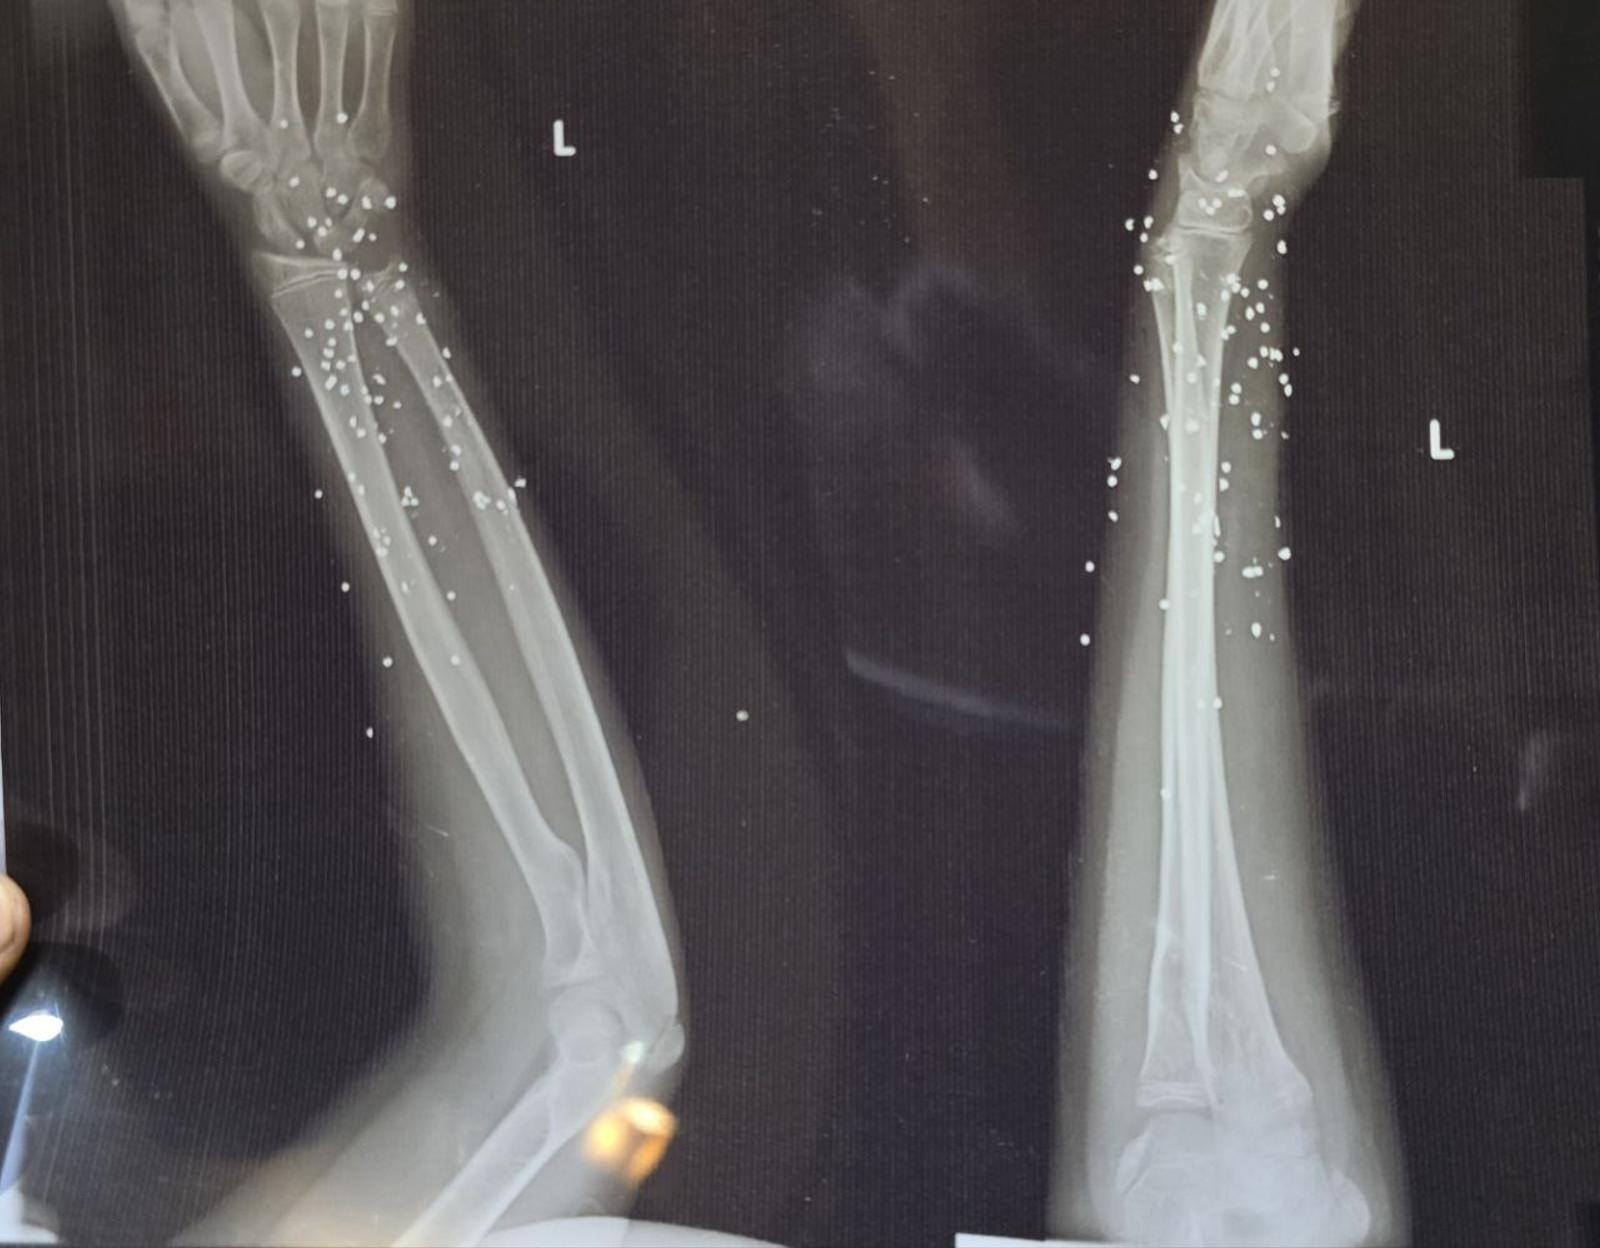

به گزارش روزنامه گاردین، بررسی دهها تصویر پزشکی ثبتشده در جریان سرکوب اعتراضات در ایران نشان میدهد معترضان با ساچمههای فلزی و گلولههای کالیبر بالا هدف قرار گرفتهاند. تصاویری که به گفته کارشناسان، از شدت جراحات و الگوی اصابت به نواحی حیاتی بدن حکایت دارند.

تصویر او یکی از بیش از ۷۵ مجموعه تصویر پزشکی شامل رادیولوژی و سیتیاسکن است که از یک بیمارستان در یکی از شهرهای بزرگ ایران به دست آمده و در اختیار گاردین قرار گرفته است. تصاویری که در طول یک شب و همزمان با سرکوب اعتراضات دیماه ثبت شدهاند.

ایران از معدود کشورهایی است که نیروهای امنیتی آن از ساچمه فلزی علیه شهروندان و برای سرکوب معترضان استفاده میکنند. هرچند هر ساچمه بهاندازه گلوله جنگی قدرت تخریب ندارد، اما تعداد زیاد آنها میتواند آسیبهایی بسیار شدید ایجاد کند.

در موارد دیگر، صدها ساچمه در بدن پراکنده شده و بافت نرم را تخریب کردهاند.